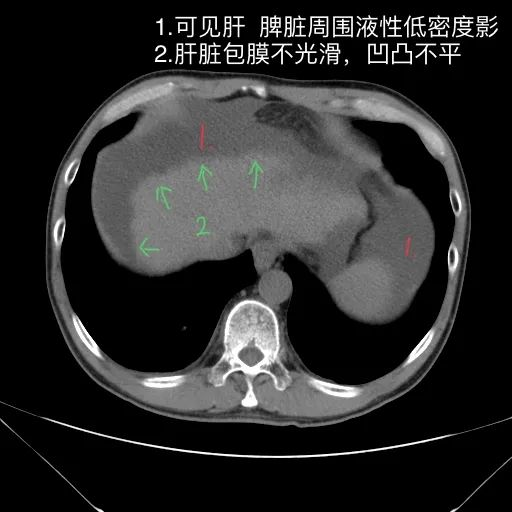

如上是肝硬化失代偿的典型表现。但没有门脉增宽和脾大表现。此外肝S4的小片低密度影除考虑为囊肿或镰旁假病灶外,还需警惕肿瘤?

肝脏缩小,包膜凹凸不平,肝裂增宽,各叶比例失衡,肝实质密度不均,肝S4小片低密度影,约cm;胆囊不大,其内未见异常密度影,胆道系统未见扩张;胰腺、脾脏形态、密度、大小未见异常;双肾上腺及双肾形态、密度、大小未见异常,双输尿管未见扩张,膀胱充盈良好,壁光滑,其内未见异常密度影;前列腺未见异常;胃肠道未见充盈,壁未见明确增厚,食管胃底多发迂曲、增粗血管,腹部及腹膜后未见肿大淋巴结;腹水。

1.肝硬化失代偿表现(腹水,食管胃底静脉曲张)。

2.肝S4小片低密度影,建议复查或进一步检查。